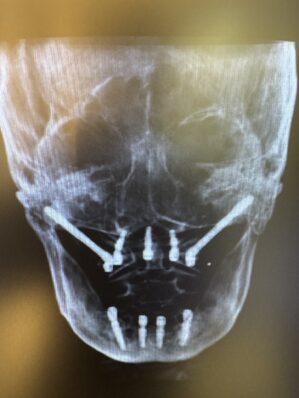

今回は10年以上前に行われた全顎のインプラントが弱ってしまいお痛みの主訴で来院された患者さん。

ザイゴマにてリカバリーを行う症例でした。上顎を4本のザイゴマインプラントで治す予定でしたが、ギリギリ前歯が使えたため上を5本、下顎を4本のインプラントを用いて即日で治療しました。